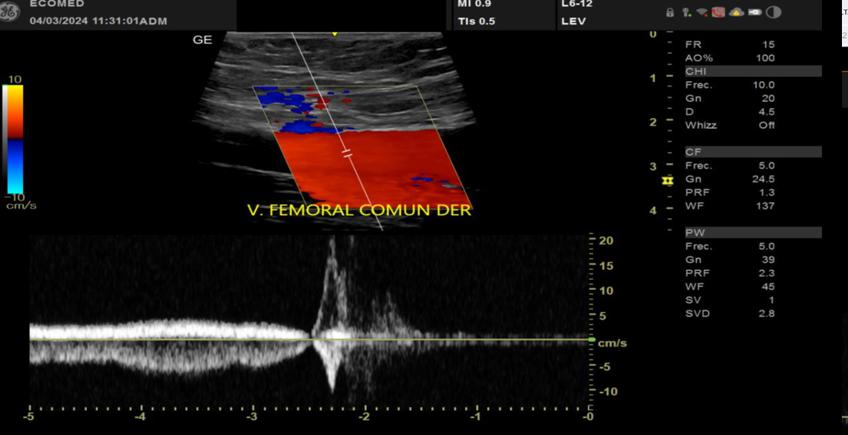

Una ecografía Doppler es un tipo de ultrasonido que utiliza ondas sonoras para mostrar qué tan bien circula la sangre a través de sus vasos sanguíneos. Puede utilizarse para examinar la circulación sanguínea en muchas partes de su cuerpo, incluyendo muchos de sus órganos, su cuello, brazos y piernas.